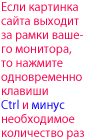

1. Локтевая кость 2. Лучевая кость 3. Пястные кости 4. Фаланги пальцев 5. Большеберцовая кость 6. Малоберцовая кость 7. Таранная кость 8. Пяточная кость 9. Плюсневые кости 10. Фаланги пальцев 1. Ulna 2. Radius 3. Ossa metacarpi 4. Ossa digitorum - phalanges proxima 5. Tibia 6. Fibula 7. Talus 8. Calcaneus 9. Ossa metatarsi 10. Ossa digitorum-phalanges proximales-stopy |

1. Лопатка